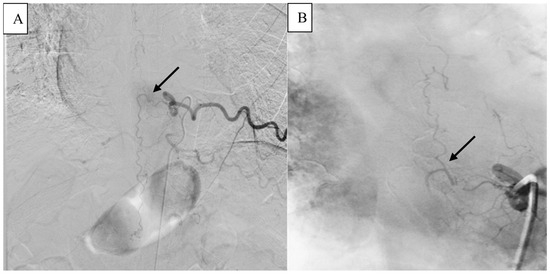

2. Detailed Case Description